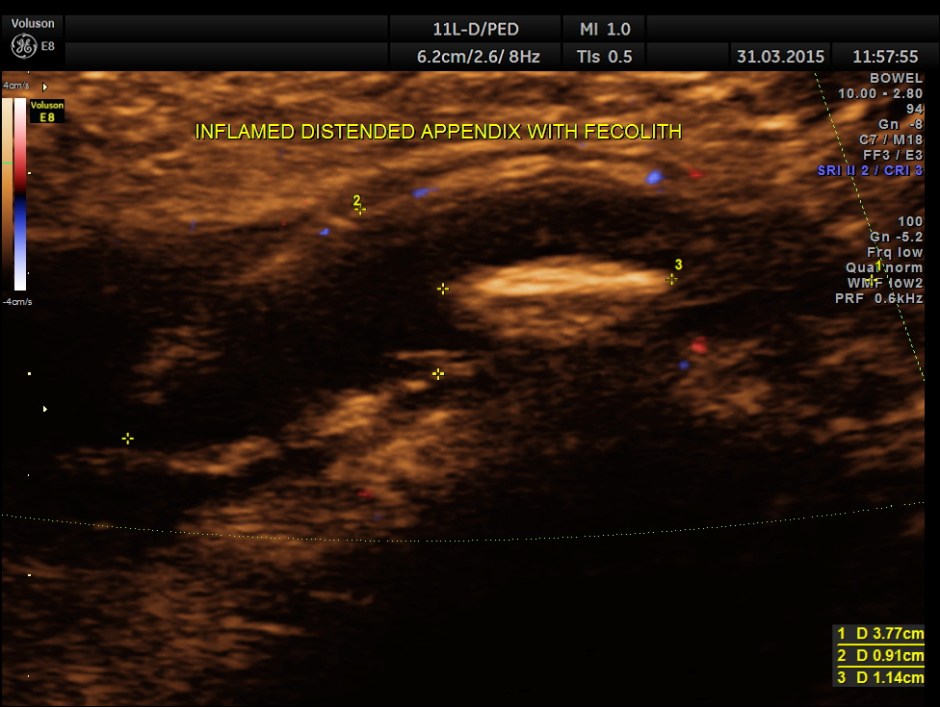

Scan ( with a regular abdominal probe ) over RIF shows an echogenic object with posterior acoustic shadowing within a dilated ” tube ” .

Colour Doppler shows vascularity of the wall . It was non pulsatile and non collapsible.

Now this looks more like an inflamed appendix with a prominent fecolith of size 11.4 mms , throwing a shadow.

The following pictures are with a high resolution probe.

The following picture shows the long and short axis views.